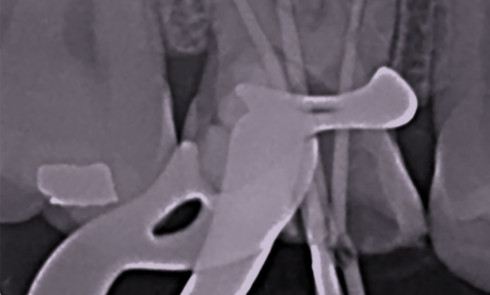

Article réservé à nos abonnés La fracture instrumentale en endo : faute ou aléa thérapeutique ?

Chaque année, la MACSF publie un rapport sur la sinistralité des professionnels de santé. En 2019, 225 sinistres de fractures...